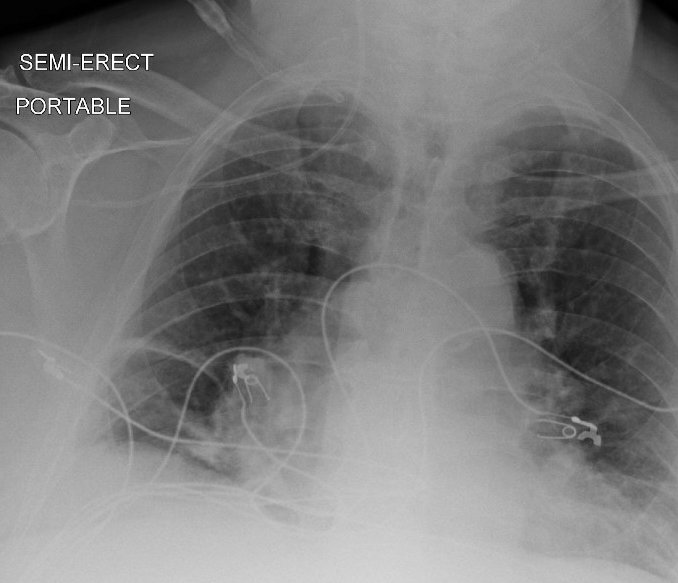

#POCUS

What is the major pathology in these clips?

How do you proceed? #abdominalultrasound will help and save lives!! @ASRA_Society @ESRA_Society @AoraIndia @WilliamMansonMD @shaskinsMD @Wilkinsonjonny @NarouzeMD @iceman_ex @ICUltrasonica @icmteaching @RJonesSonoEM